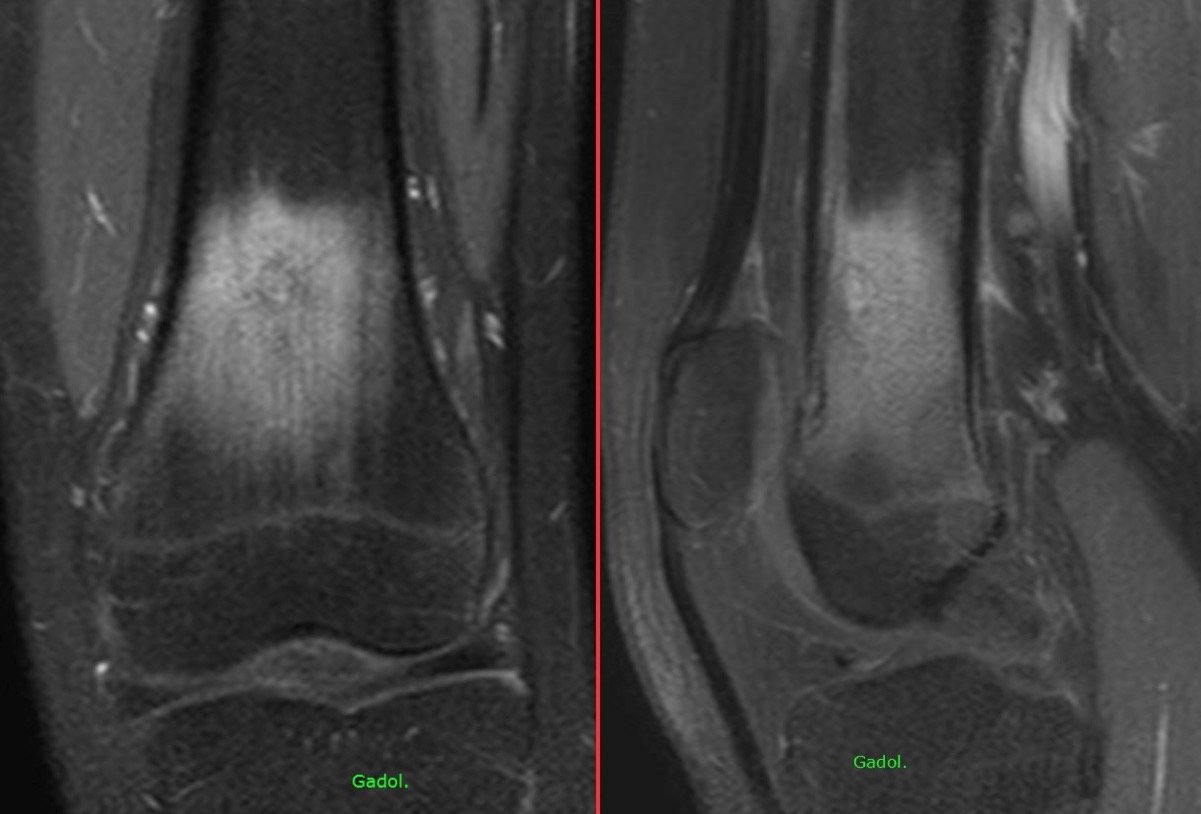

Figure 1 for case osteoid osteoma ( RID4005 )

Figure 1

Figure 2 for case osteoid osteoma ( RID4005 )

Figure 2